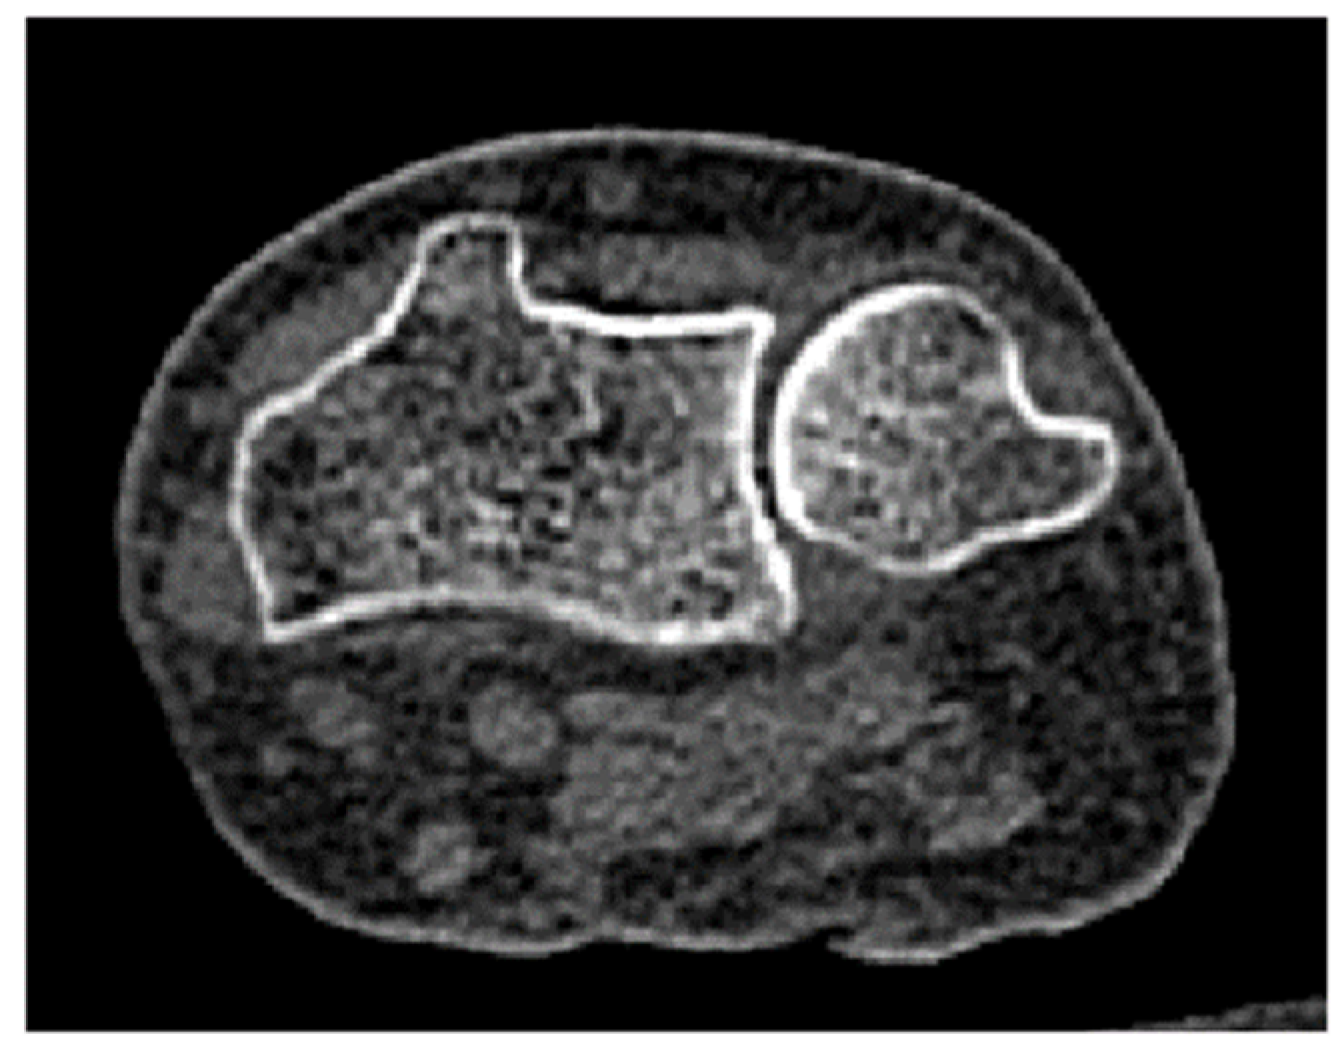

2.2. Three-Dimensional Modeling

2.3. Bone Material Properties Assignment